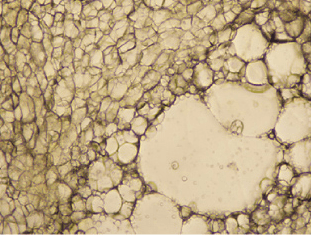

脂肪细胞呈现为均匀细小的泡状。

被溶解的区域开始出现并扩散开来。 周围的血管不受影响,血液的流动得以保证。

脂肪细胞的细胞膜破裂,存在于被称作油滴的储藏库中的中性脂肪,随着时间的推移被溶解出来,并随着血液或淋巴系统排出,或者作为能量被消耗掉。